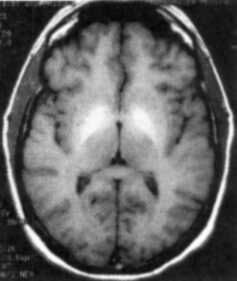

I would like to mention some chapters which I found of special interest. In the chapter on clinical neurotoxicology, we are told that several toxins can actually be diagnosed by CT and MRI. There is even a table which tells us of the various toxins which can be detected by these methods. There are pictures showing MRI scans of brain showing deposition of manganese in the basal ganglia area. These areas are seen as bright oval areas. Other poisons which can thus be detected (i.e. either by CT or MRI or both) are methanol (putamen and globus pallidus lesions), toluene (loss of differentiation of gray and white matter, cerebral and cerebellar atrophy and a host of other changes), Hydrogen Peroxide (Ischemic changes and cerebral infarction), organic solvents (cerebral atrophy) and Carbon Monoxide (basal ganglia lesions, particularly globus pallidus and white matter lesions).